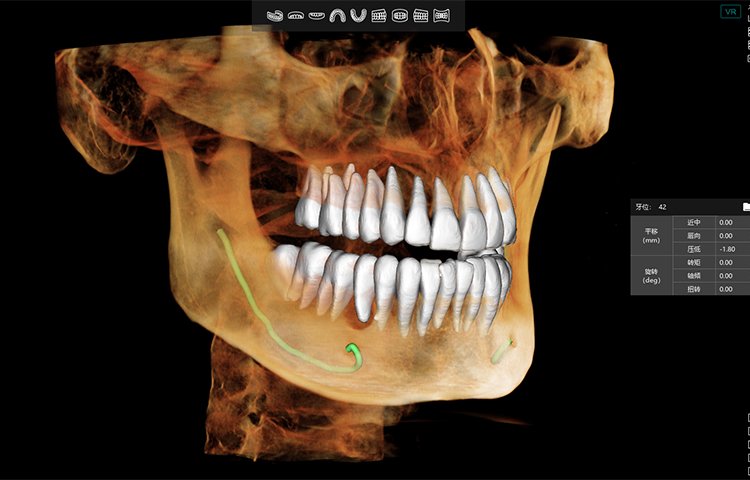

El software de diagnóstico 3D líder de Meyer y el sistema de análisis ortodóntico inteligente adoptan un diseño de UI modular, lo que hace que las funciones del software sean más cercanas a las necesidades clínicas y más fáciles de usar para los médicos, reduciendo significativamente el costo de aprendizaje.

Software de Diagnóstico 3D

MyDentViewer